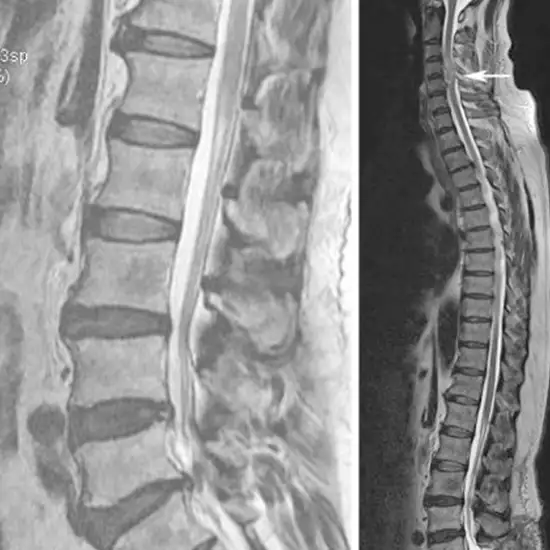

What is MRI Screening of the LS Spine?

A lumbar MRI looks at the lower part of your spine, where most back problems start.

MRI (Magnetic Resonance Imaging) screening of the ls spine is a non-invasive radiology test used to evaluate the condition of the LS spine and surrounding tissue. MRI Screening of the LS Spine is done to look for the condition of the LS spine and surrounding area.